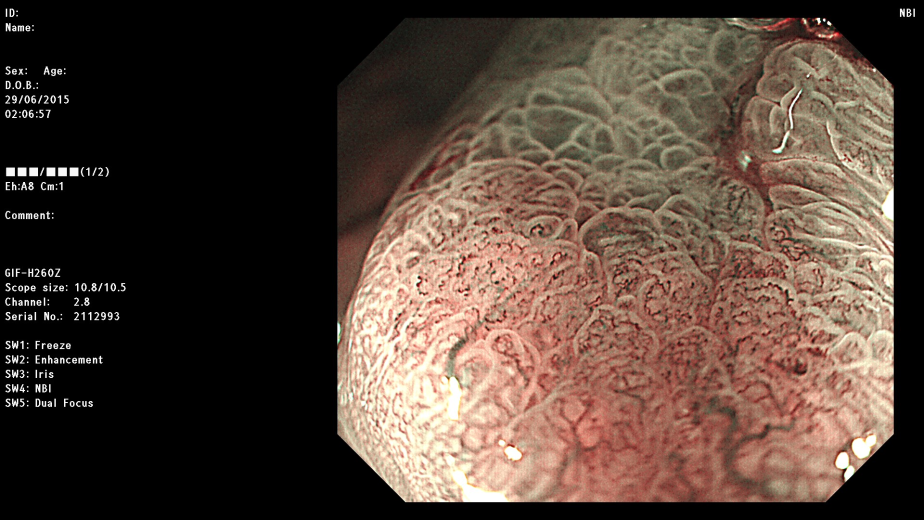

现在,胃镜检查不仅仅是感觉轻松,更主要的是胃镜检查设备的革新和升级,在原本的电子胃镜基础上开展了NBI技术(Narrow Band Imaging,NBI,窄带成像)以及放大染色技术等,医生观察到的胃粘膜是那么的清晰明了,微小至1-2毫米的病灶也逃不出新技术的“火眼金睛”,使得极为隐蔽的毛病,尤其是极早的胃癌都能发现,这才是新一代胃镜的最大价值所在。可以预测,随着胃镜新技术的普及,早期的胃癌都可以发现,也就都可以治愈,胃癌就成为可治愈的癌症之一。发现一例早癌,挽救一个生命,幸福一个家庭,安宁一片天空。

新技术胃镜所见 (有病变处显示清楚的深颜色斑片)

再放大后的观察